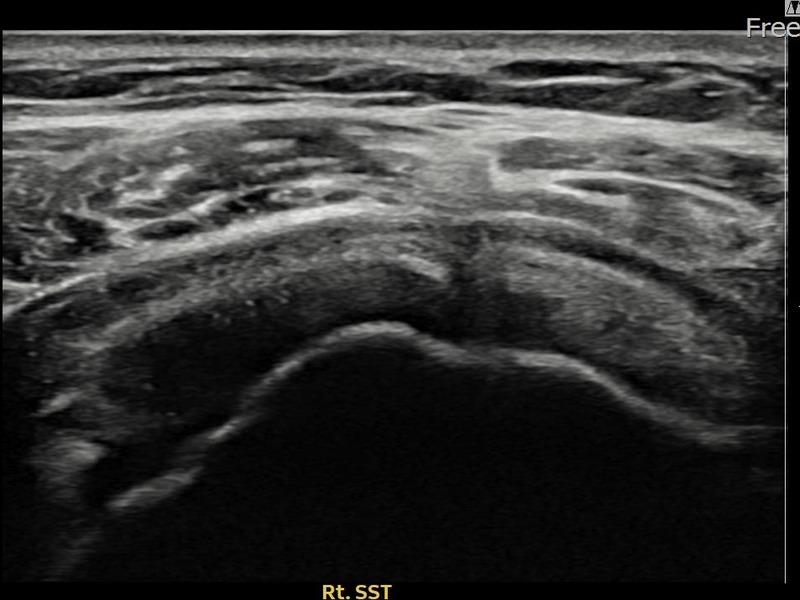

최ㅇㅇ님 · 우측 극상근건 관절면측 파열 진행형

우측 어깨 파열이 진행된 상태로 수술 없이 치료를 원해 내원하셨습니다. 다각도 초음파 평가 후 축소봉합술을 시행하여 힘줄 구조가 안정화되었습니다.

상세 보기 →